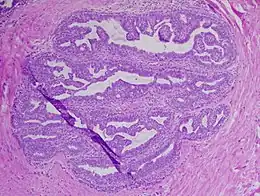

Papillome intracanalaire du sein

Le papillome est une petite tumeur bénigne constituée d'axes conjonctifs bordés par des cellules épithéliales.